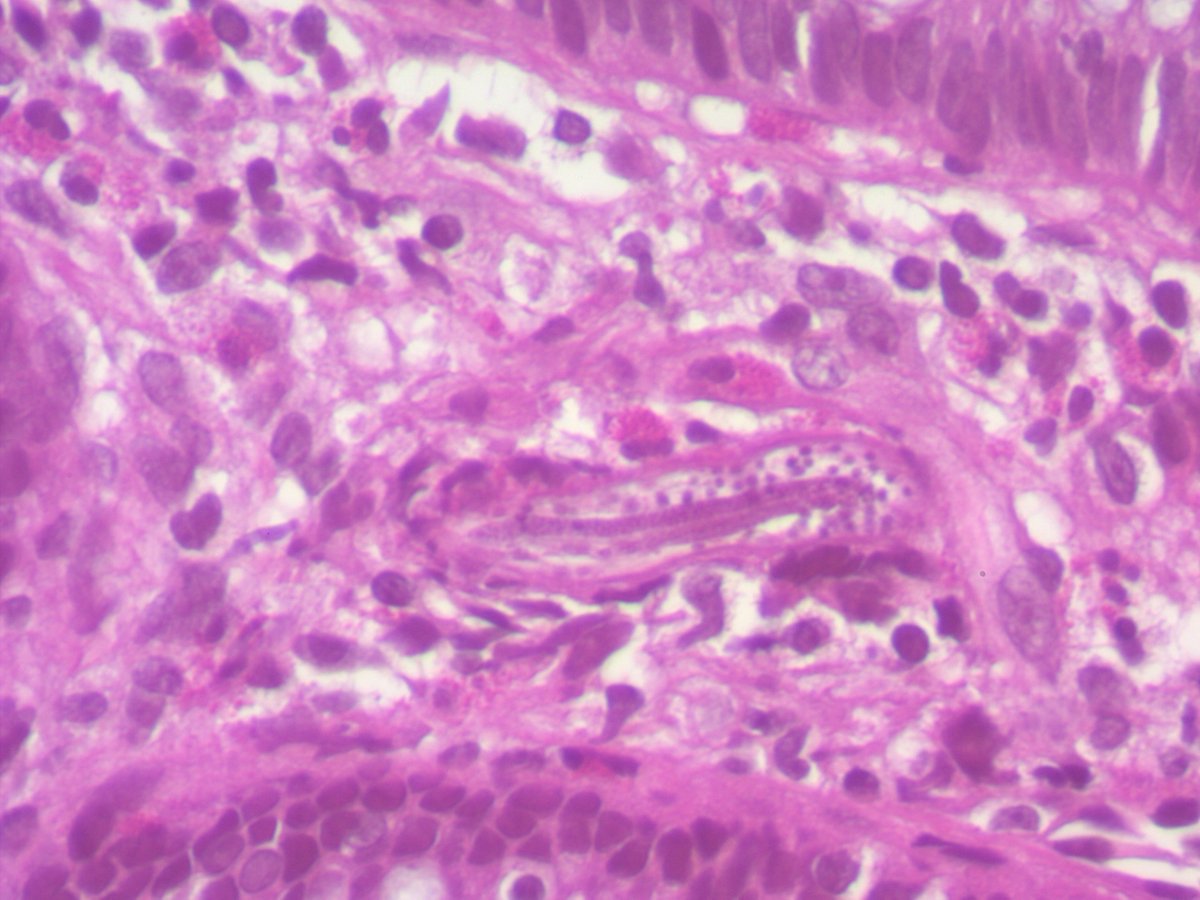

Any thoughts on this beautiful, elegant creature that "crawled" into the colonic mucosa and presented as polyp !! I have been googling it for ages and can't find a morphologic fit with any of the adult/ larval parasitic forms that I have ever encountered. Pt is asymptomatic.